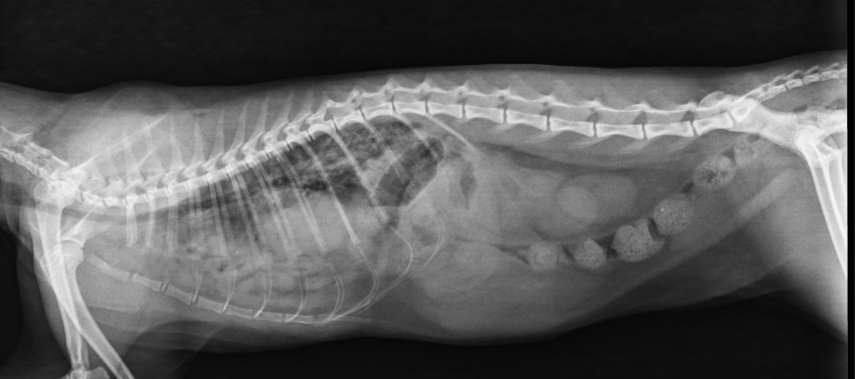

INTESTINO GRUESO – COLON

PERRO: diámetro normal < longitud L7

GATO: diámetro normal < 1,5 × L7

Signo de interrogación en ventrodorsal

MEGACOLON – CONSTIPACIÓN

OTRAS ALTERACIONES

- Engrosamientos: Inflamación, Neoplasia